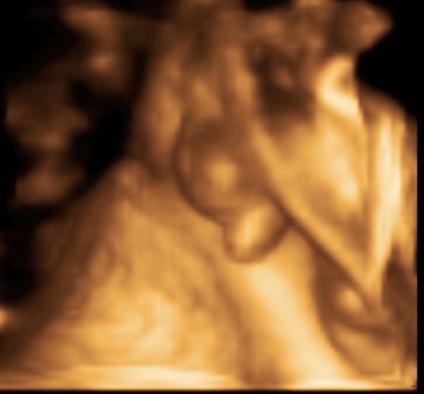

UZV

transvaginalni

transabdominalni